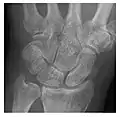

Figure 3: A 26-year-old man presenting with wrist pain after being assaulted. (a) Initial anteroposterior radiograph shows a subtle linear lucency within the scaphoid extending to the scaphocapitate articular surface that was overlooked (arrow). (b) Initial "scaphoid" view was negative. (c) Followup anteroposterior radiographs, 12 days later, shows obvious scaphoid fracture (arrows).[1]

Triquetral fracture usually occurs on the dorsal aspect by impingement from the ulnar styloid or avulsion of strong ligamentous attachment. The dorsal avulsion fracture or "chip fracture" appears as a small bony fragment on the dorsal aspect of the triquetrum and is best detected on the lateral view(Figure 4). When radiography is negative in patients with high suspicion of a fracture, both MRI and MDCT will be of value. However, it has been shown that MRI is superior for detecting trabecular fractures in carpal bones.